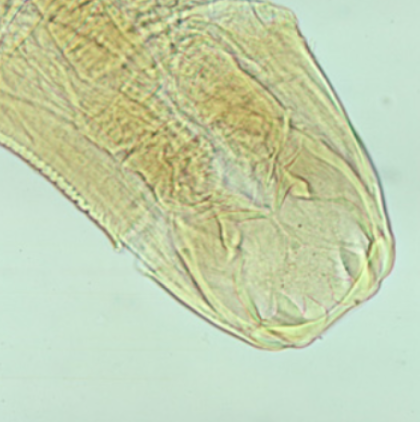

43

New cards

Ancylostoma duodenale (Old world hookworm) mouth

knowt flashcard image